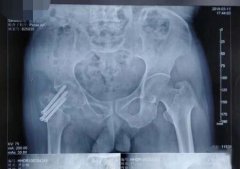

鄂州市中心医院骨二科顺利完成我市首例仿生双动全髋关节置换